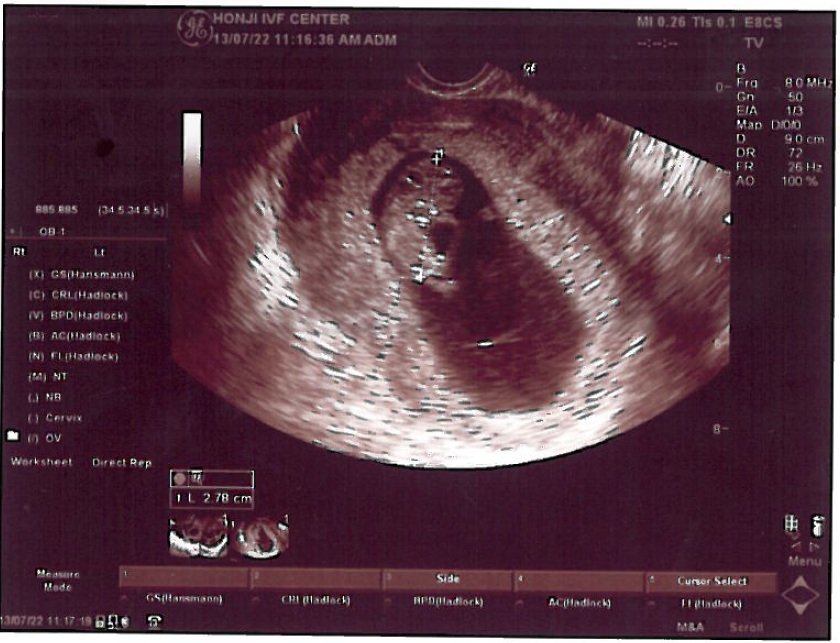

我們是上月在你那畢業的夫妻(懷孕滿9周)!

現在寶寶很健康長大,真得很感謝你們團隊。

這次在張醫師的精湛的手術、實驗室團隊的優良品管、懷孕初期的少量但精準的藥物與數據控制,這次我們終於懷孕了,聽到心跳的那一剎那,使我們體會到非常深刻的生命意義!